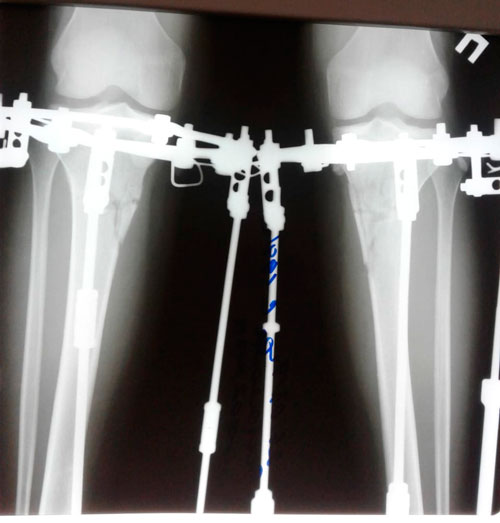

Исходник - 28 лет. Шымкент.

Дата операции - 05.03.2019г.

Дата снятия аппаратов - 26.06.2019г.

Срок сращения - 110 дней.